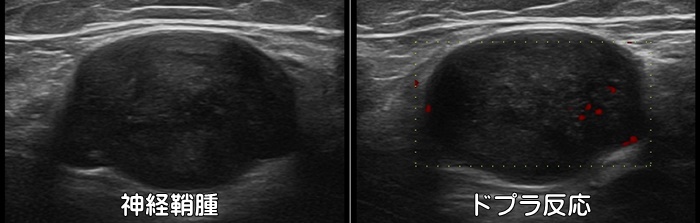

神経鞘腫

末梢神経由来の代表的な良性の軟部腫瘍です。膝裏にできた場合は“しこり”として触知され、ベーカー嚢腫との鑑別が必要です。神経鞘腫は押すと痛みがあったり、叩くと足先まで電気が走るような痛みがあります。場合によっては手術で切除します。